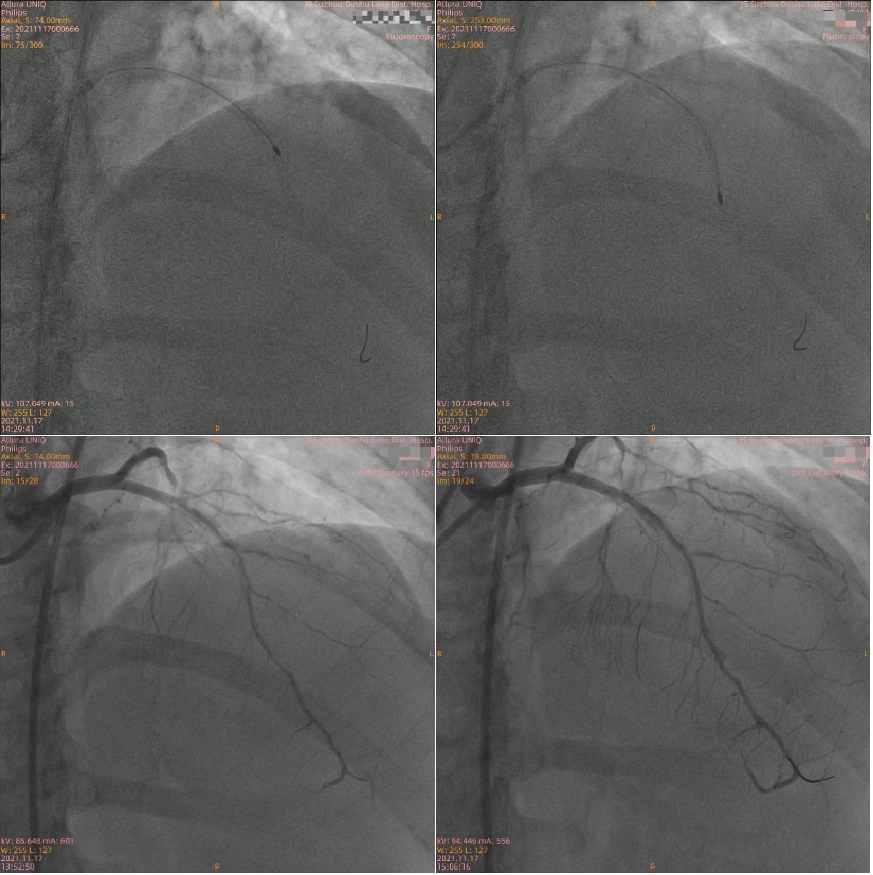

53岁的林女士常感觉活动后胸闷、胸痛,1个月前在当地医院诊断为冠心病,经冠脉造影检查可见冠脉三支病变且伴有严重钙化。当地医生没有尝试介入治疗,建议患者行冠脉搭桥手术。患者及家属考虑到搭桥手术需要开胸,创伤大,思虑再三拒绝了外科手术。转至我院后,找到了周亚峰副院长,周亚峰副院长所带领的介入团队研读冠脉造影影像,制定了血运重建策略:分两步介入。即先为钙化相对较轻的RCA(右冠)及LCX(左旋支)两根血管行介入治疗后,再针对造影所示钙化非常重的LAD(左前降支)行OCT检查,必要时行旋磨治疗。

二次介入手术中,团队应用OCT检查血管,血管腔内的结构一览无余。可见LAD管腔内钙化角度大(270°-360°)、钙化非常厚(>1mm)、钙化弥漫(>20mm),钙化评分达到最高分值(CVI:4分),团队决定首选旋磨治疗。LAD应用1.25mm、1.5mm旋磨头以160000转/分的速率高速旋磨,重度狭窄的LAD最终被开通。严重狭窄的血管恢复了畅通,术后林女士胸闷、胸痛症状感到明显好转。